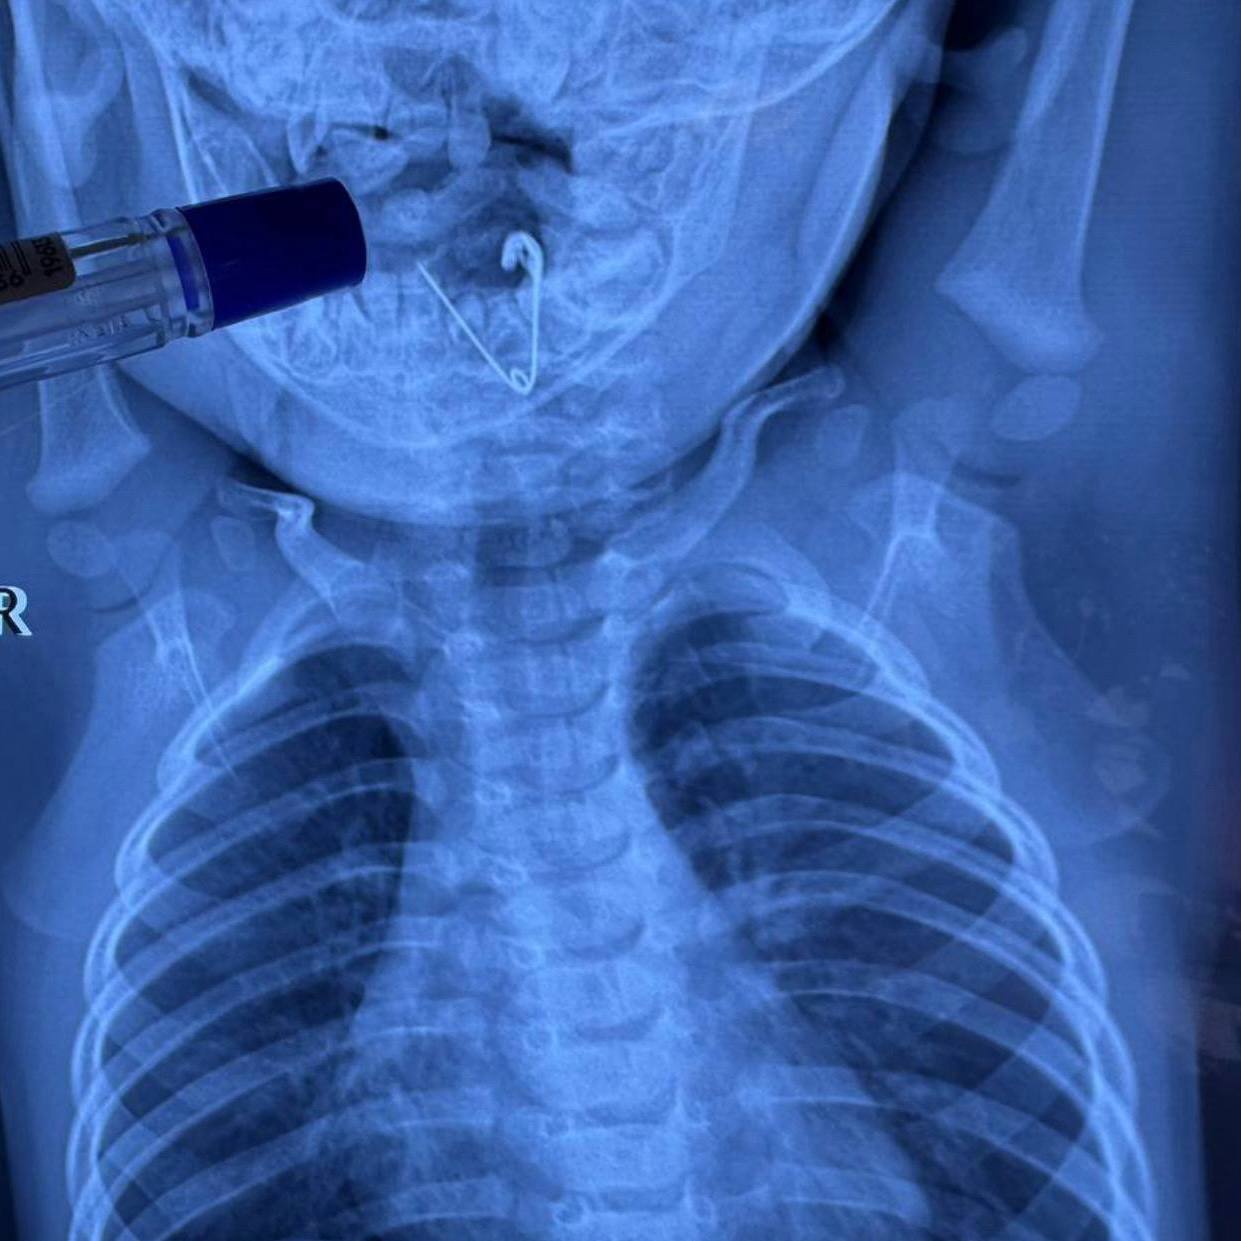

В Приморье врачи спасли семимесячного малыша, проглотившего открытую булавку. У ребенка внезапно начались кашель и слюнотечение, после чего родители обратились за помощью.

С помощью эндоскопа медики краевой детской больницы извлекли опасный предмет из пищевода. Состояние малыша нормализовалось.